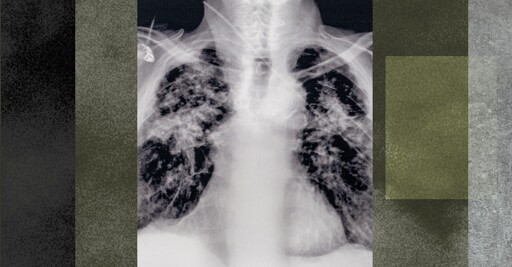

Silicosis is no fucking joke. I watched my father die to fibrosis, which is very similar. He went from an energetic and active retiree to a chair bound and weak man in a matter of weeks. He lived the rest of his life barely able to walk from his car to the scooters to go grocery shopping. Doing so much as turning a valve to shut off the water to his sprinklers would have taken him an hour or more, and he wouldn’t have been able to do much else that day.

He lived for 2 of the 5 years he thought he had fighting for every single breath. All day. Every day.

The worst workplace disaster in US history was silicosis.